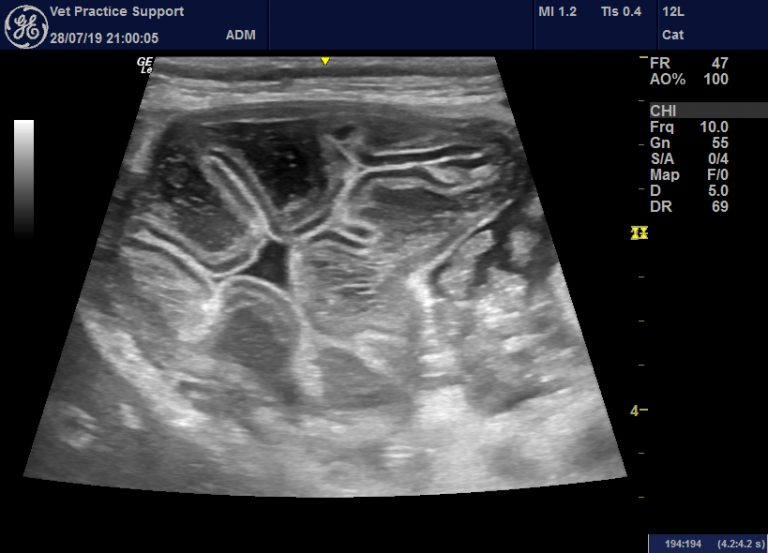

What Causes Thickening Of The Intestinal Wall In Dogs. inflammation of the stomach and intestine can cause acute and chronic symptoms of digestive upset. The term ibd is used to describe a group of conditions characterized by inflammation of the gastrointestinal tract and persistent or recurrent gi signs. abdominal ultrasound revealed diffuse, generalized thickening of the gastric wall (up to 1.5 cm), with a focal, marked. It is not possible to differentiate. they may also detect enlarged organs that could indicate organ dysfunction. inflammatory bowel diseases are the most common cause of chronic vomiting and diarrhea in dogs and cats. Ultrasound may be able to pinpoint thickened tissue regions that may. In this blog, we look into what inflammation of the intestines in dogs is, the causes of stomach inflammation and thickened intestinal walls,. ibd can cause focal or diffuse thickening of the intestinal wall, with or without loss of wall layering. in intestinal incarceration, a loop of bowel becomes stuck through a weak spot in the body wall (hernia), causing it to swell and trap digested food inside.

inflammatory bowel diseases are the most common cause of chronic vomiting and diarrhea in dogs and cats. they may also detect enlarged organs that could indicate organ dysfunction. ibd can cause focal or diffuse thickening of the intestinal wall, with or without loss of wall layering. abdominal ultrasound revealed diffuse, generalized thickening of the gastric wall (up to 1.5 cm), with a focal, marked. in intestinal incarceration, a loop of bowel becomes stuck through a weak spot in the body wall (hernia), causing it to swell and trap digested food inside. The term ibd is used to describe a group of conditions characterized by inflammation of the gastrointestinal tract and persistent or recurrent gi signs. In this blog, we look into what inflammation of the intestines in dogs is, the causes of stomach inflammation and thickened intestinal walls,. It is not possible to differentiate. Ultrasound may be able to pinpoint thickened tissue regions that may. inflammation of the stomach and intestine can cause acute and chronic symptoms of digestive upset.